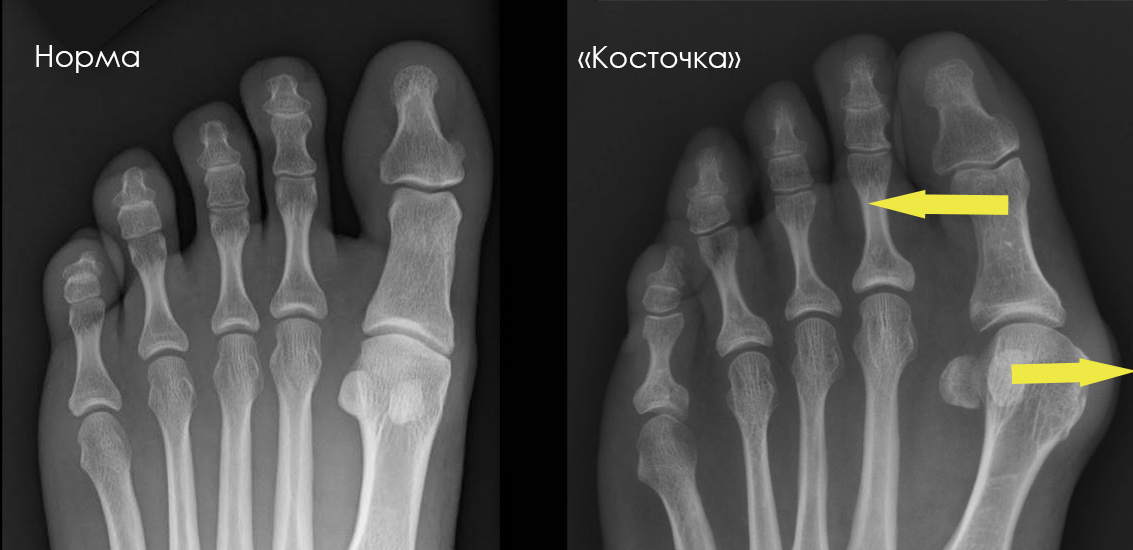

Мы уже обсуждали в прошлом посте, что "шишка" - это не просто костный нарост, а изменение положения костей стопы, что хорошо видно на рентгене:

Пример рентгенограмм стопы в прямой проекции до (слева) и после (справа) остеотомий scarf и Akin